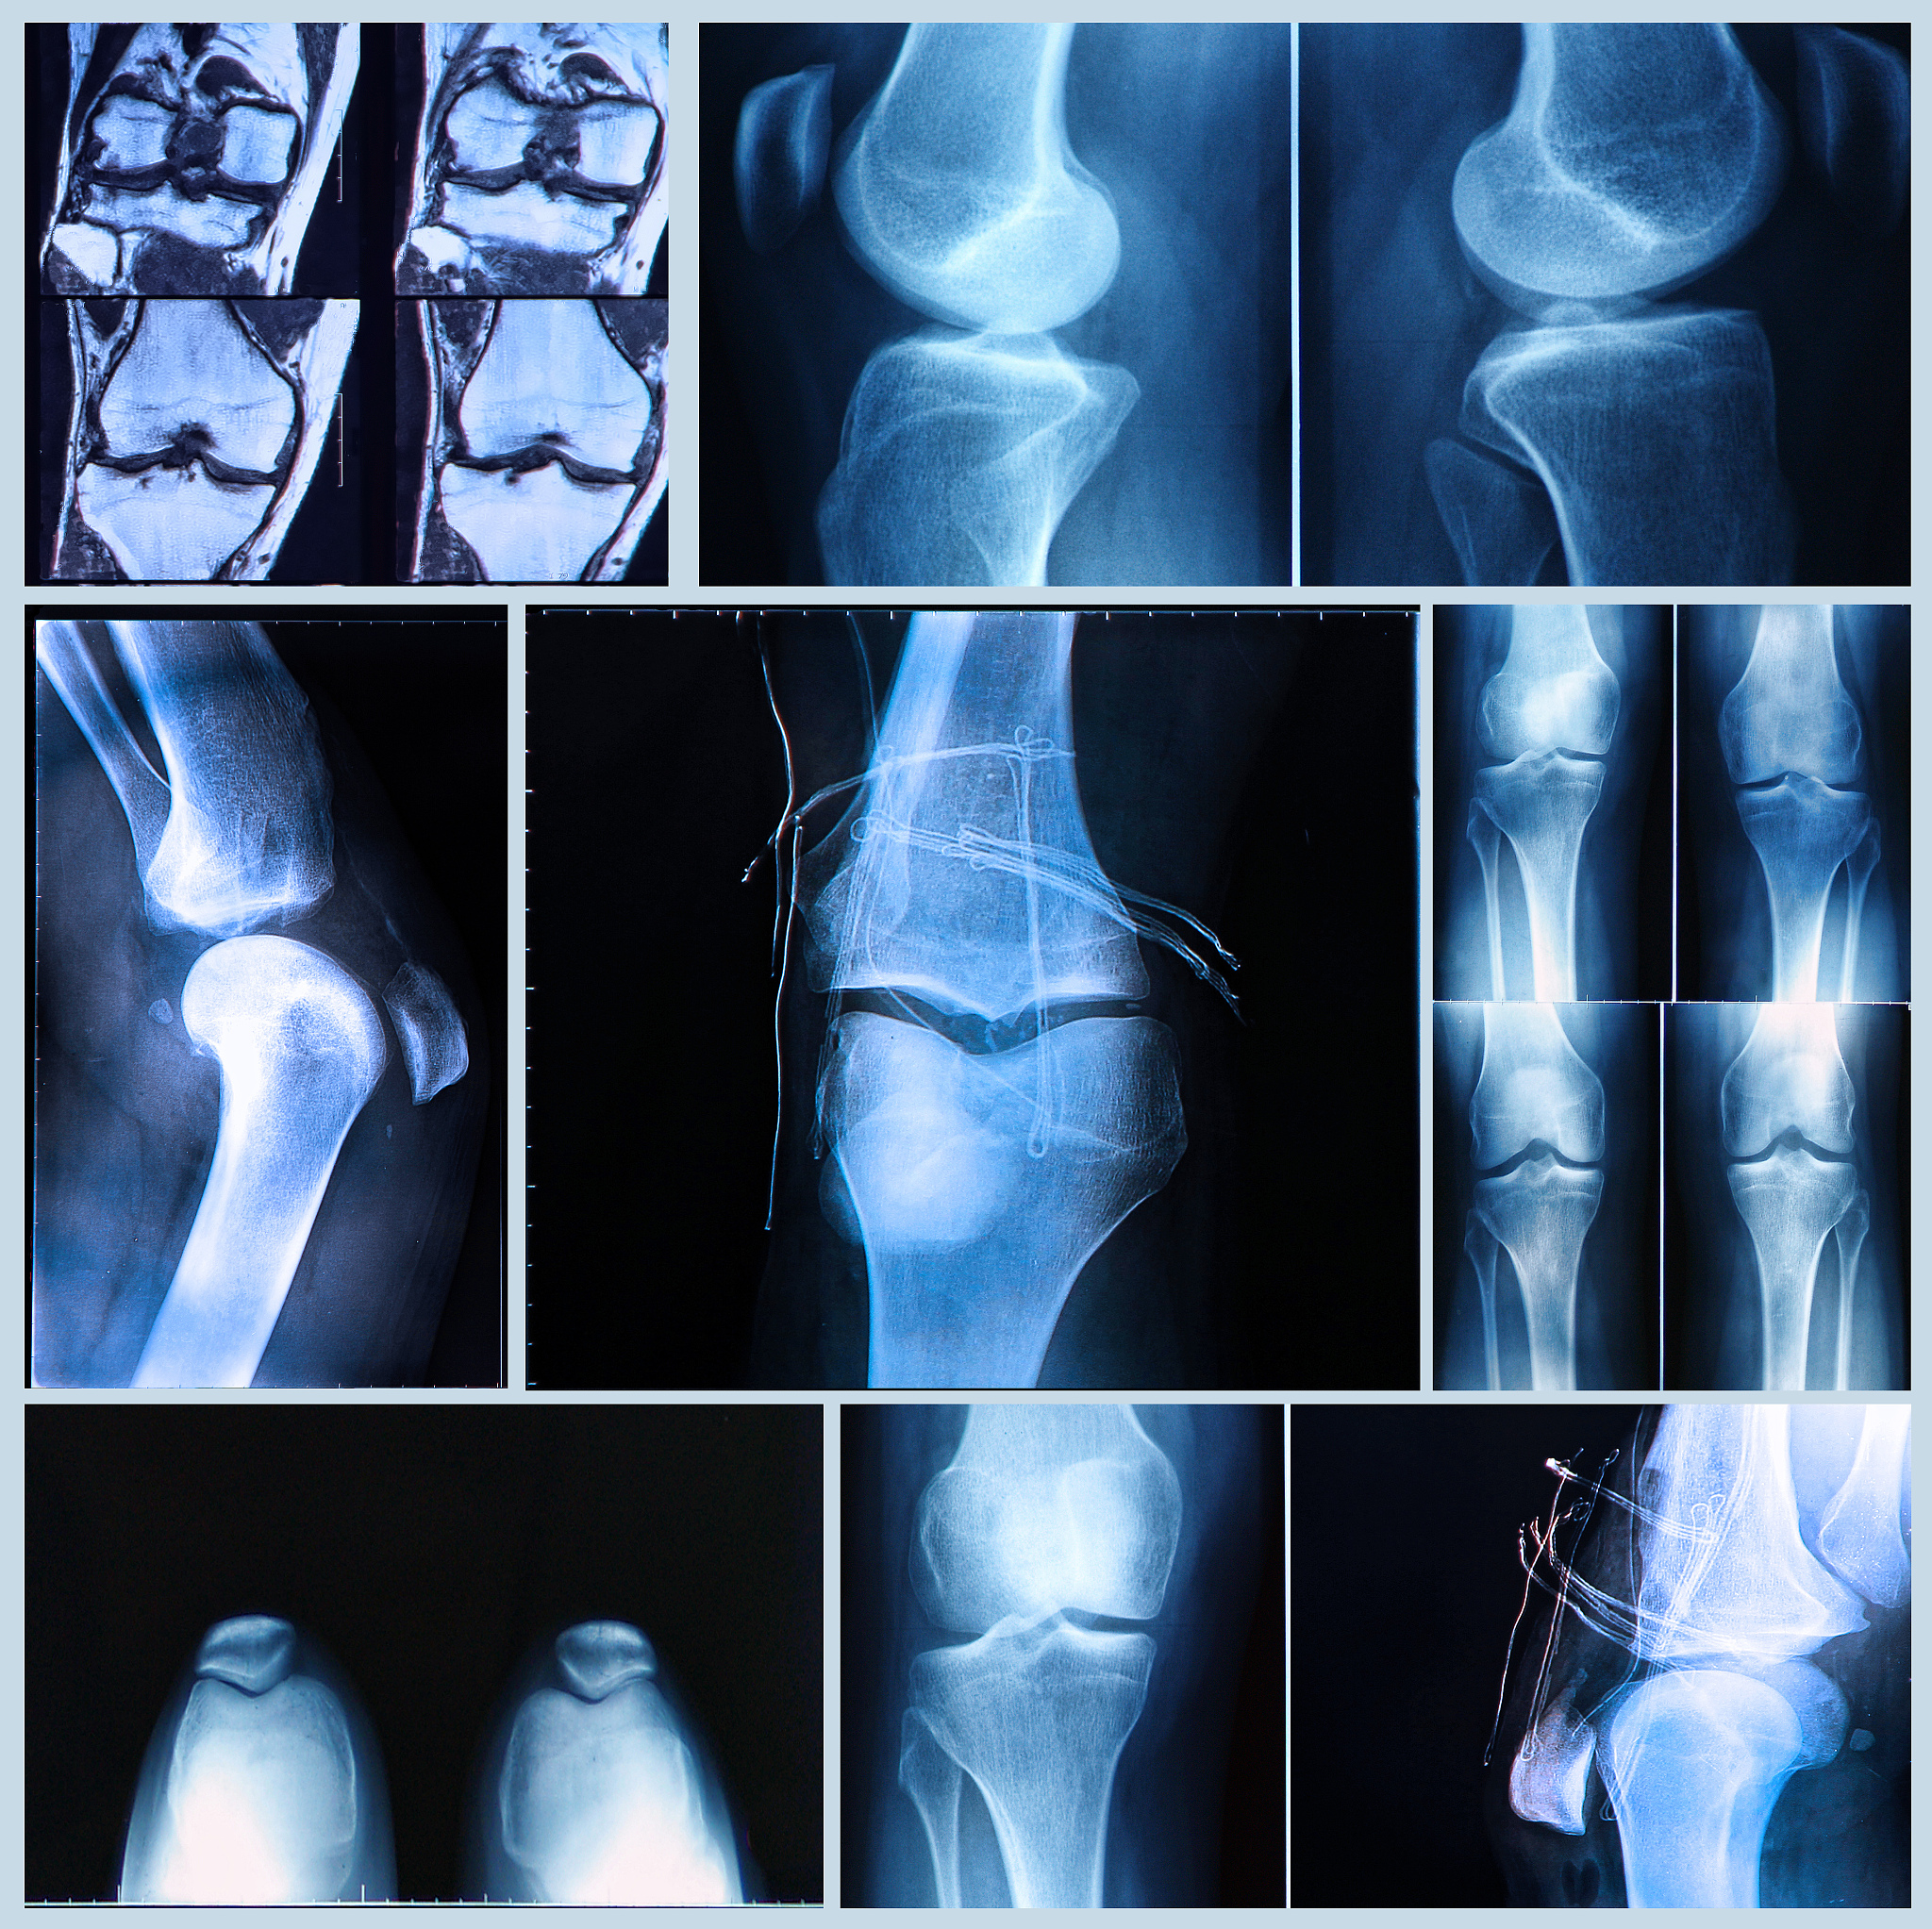

韧带损伤分级:MRI表现及恢复情况

韧带损伤根据MRI检查结果可分为三级:

• **Ⅰ级:**韧带肿胀减轻,高信号减弱或范围缩小,部分中断,关节腔有积液;

• **Ⅱ级:**韧带稍肿胀,高信号明显减弱或范围明显缩小,连续性存在,关节腔少量积液;

• **Ⅲ级:**韧带基本无肿胀,信号正常或轻度不均匀,关节腔内无或少量积液。

Ⅰ级韧带损伤表明韧带轻微受损,可能需要休息和保守治疗即可恢复。

Ⅱ级韧带损伤表示韧带部分撕裂,需要更长时间的休息和物理治疗,并可能需要佩戴护具来固定关节。

Ⅲ级韧带损伤意味着韧带完全断裂,通常需要手术治疗,并进行长时间的康复训练。